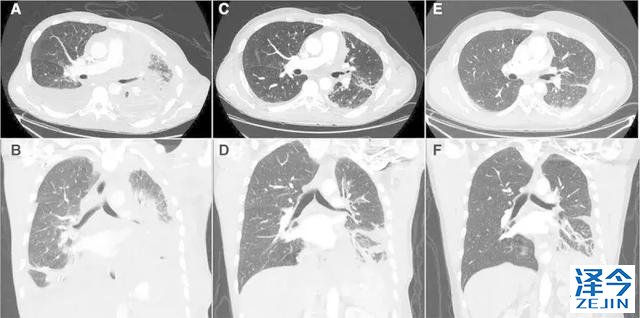

一位77岁的女性患有EPS15-NTRK1 IV期非小细胞肺癌,我们可以看到她的双肺满是病灶,并且出现了肝脏和脑转移,可以说是非常非常晚期了,

既往有乳腺癌史;

既往症状有厌食,乏力,咳嗽,高脂血症;

ECOG 1;

没有接受手术,放疗或化疗。

开始使用larotrectinib 100 mg BID并持续治疗,

第3周期开始:

肺靶病变达到缓解,我们可以明显的看到前后的图像,病灶明显缩小了,

脑转移病变显示缩小了95%!

初始, 2018年6月 3周期 2018年8月